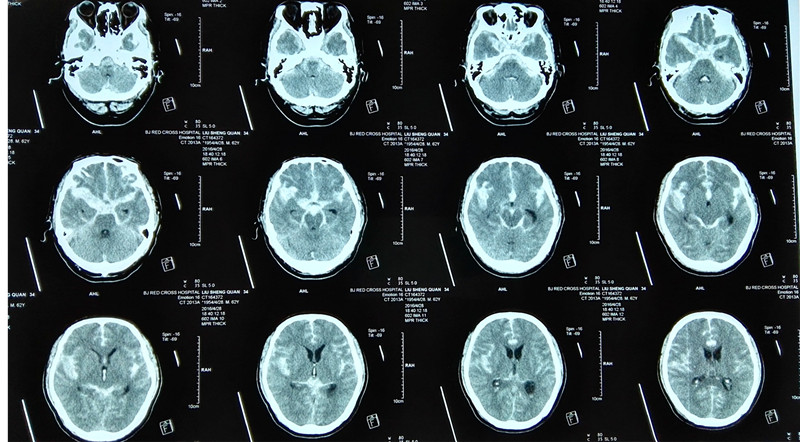

清华长庚医院7月29日电(通讯员 马春岳)刘叔叔原本是一名退休大学教师。辛苦工作一辈子,终于有时间和老伴享受生活,含饴弄孙。不料,3个月前一场突发的疾病令他的命运彻底改变,诊断为脑动脉瘤破裂,蛛网膜下腔大量出血。经过艰难的抢救和手术,虽然保住了性命,但却陷入了持续的昏迷。眼睛虽然能够睁开,却视而不见、听而不闻。四肢完全瘫痪,不能活动。浑身插满管子,连维系生命最基础的呼吸、进食和排便都不能完成,需要完全依赖护理。面对这样的情况,家人感到身心疲惫、非常绝望,难道刘叔叔的后半生注定要这样在病床上度过?抱着一线希望,刘叔叔的儿子找到了北京清华长庚医院康复医学科潘钰主任。